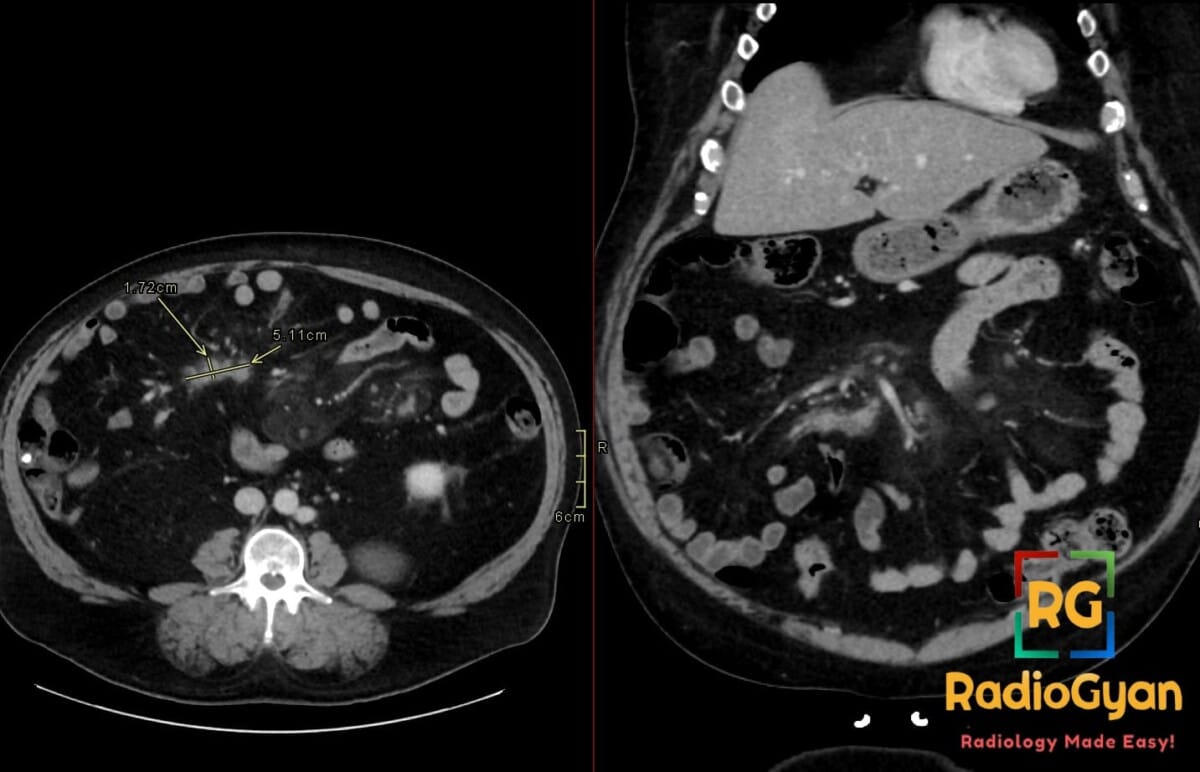

62 yr male presenting with chronic vague abdominal pain, weight loss, and a palpable right-sided abdominal fullness.

Diagnosis: Mesenteric panniculitis with developing lymphoma in the right paramidline mesentery

- The fat halo sign and tumoral pseudocapsule are hallmark CT findings of mesenteric panniculitis that help differentiate it from infiltrative processes like lymphoma.

- Evolution into lymphoma should be suspected if follow-up imaging demonstrates lymph nodes larger than 12 mm, loss of the fat halo sign, or coalescence of nodes into a solid mass.

- CT: Misty mesentery appearance with increased fat attenuation (-50 to -90 HU); well-defined mass often in the left paramidline; presence of small lymph nodes (<10 mm); development of lymphoma suggested by nodes >12 mm, nodal coalescence, and necrosis.

- Signs: Fat halo sign (preserved normal fat density around vessels/nodes); Tumoral pseudocapsule (peripheral soft-tissue band of fibrosis); Misty mesentery (hazy increased fat attenuation).